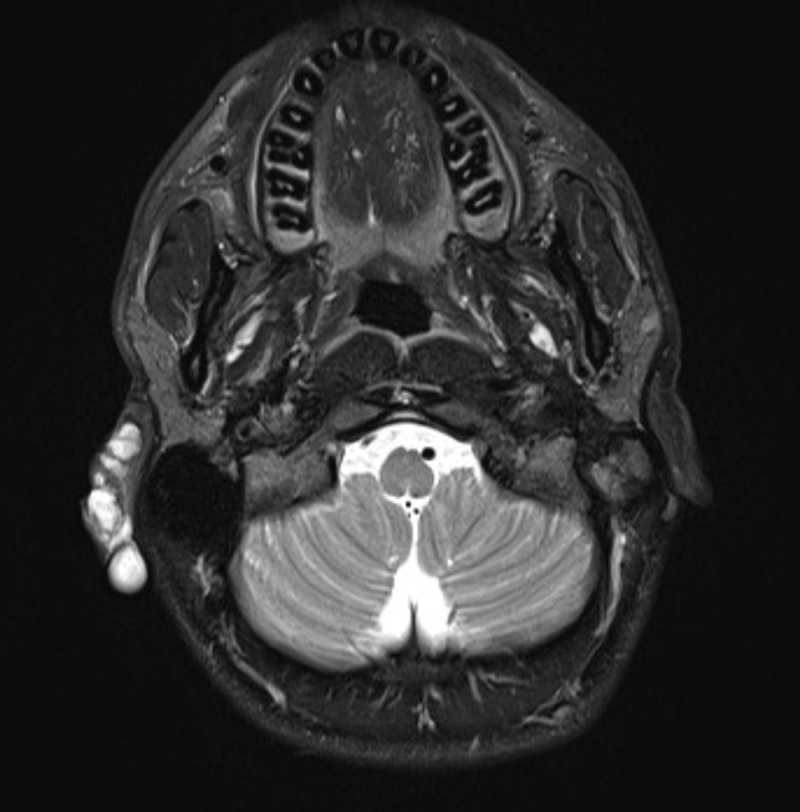

Figure 3: T2 weighted fat sat axial MRI image demonstrating a

low-flow vascular malformation affecting the right pinna.

The clinically evident portion of the lesion on examination is often only the minority of the mass volume and this is referred to as the ‘iceberg’, with the larger proportion of the lesion extending into the deeper anatomical spaces such as the parapharyngeal space, buccinator space and infra-temporal fossa [4]. This highlights the importance of a thorough imaging review to assess the full extent of the lesion and anatomical surroundings. Any treatment with sclerosants causes inflammation and swelling and this in turn can lead to compromise of adjacent structures, the most important being the airway. Imaging assessment typically consists of ultrasound and MRI. The sequences commonly used in a vascular anomalies protocol include T1 spin-echo sequences and T2 fat-saturated and / or short inversion recovery (STIR) imaging to delineate the lesion from the surrounding fat and determine its relation to surrounding structures, particularly the airway and neurovascular bundles. Post-contrast (gadolinium) MR imaging can be used but is not necessarily essential as a correct diagnosis can usually be made with clinical findings, site and the pre-contrast MR imaging [3, 5]. CT has little value in the assessment of low-flow lesions but can occasionally be of benefit if bones are involved.